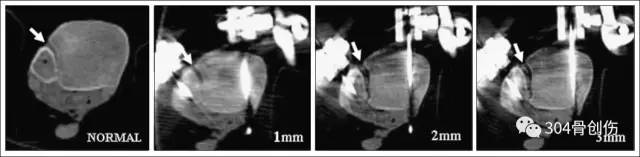

Ebraheim等证实CT扫描对下胫腓联合损伤诊断比X线平片更容易可靠,敏感性更高。Ebraheifn等对尸体标本进行CT扫描发现,大部分2mm的下胫腓分离可以通过CT扫描发现并确诊,但无法识别1mm以内分离。而X平片仅能发现3mm以上的分离。CT扫描可以克服X线片上重叠影和投照体位的干扰,轴向扫描图像上胫腓间隙内部被清晰地显示,测量相关数值与健侧对比能准确的判断是否存在下胫腓分离。

CT 诊断

Taser等认为CT三维重建可以显示下胫腓关节的容积形状和大小,在诊断1 mm以内的下胫腓联合分离即具敏感性;当下胫腓联合分离为1 mm时,下胫腓关节容积可以增加43%,当分离>3 mm后,每增加1 mm下胫腓关节容积递增20%,且推荐CT三维重建可以作为下胫腓联合损伤手术前、后完整性评估的方法。

将下胫腓前韧带切断(箭头所指)

外固定架分离下胫腓

Taser F, Shafiq Q, Ebraheim NA.Three-dimensional volume rendering of tibiofibular joint space and quantitative analysis of change in volume due to tibiofibular syndesmosis diastases. Skeletal Radiol.2006 Dec;35(12):935-41.

胫骨关节面1cm做基准面测量

分别造成1、2、3mm下胫腓分离

相距1mm扫描共计20个平面

测量平面间下胫腓容积

下胫腓分离不同,容积变化明显